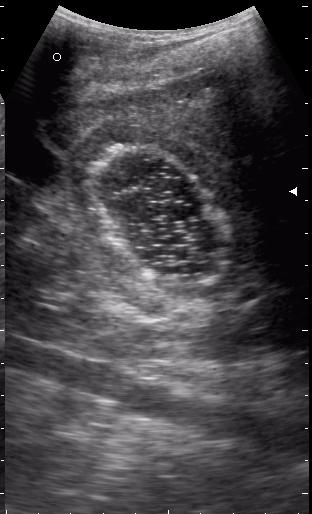

эхинококкоз печени девочка 12 лет.

живой эхинококк.